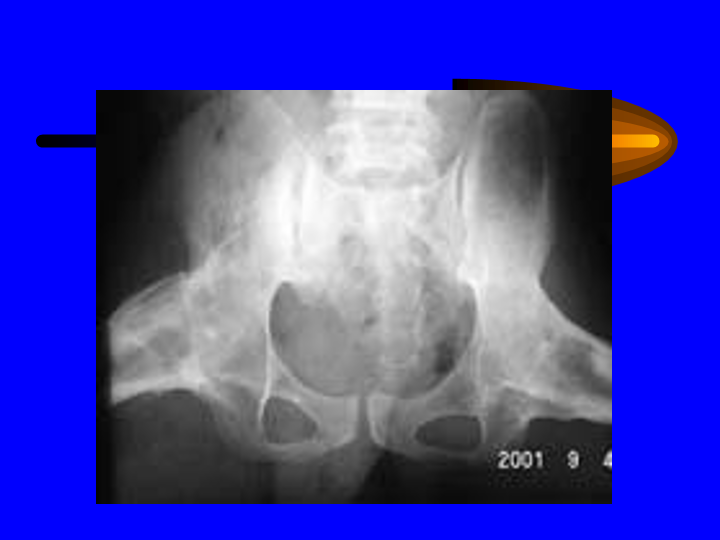

骨和关节X线诊断